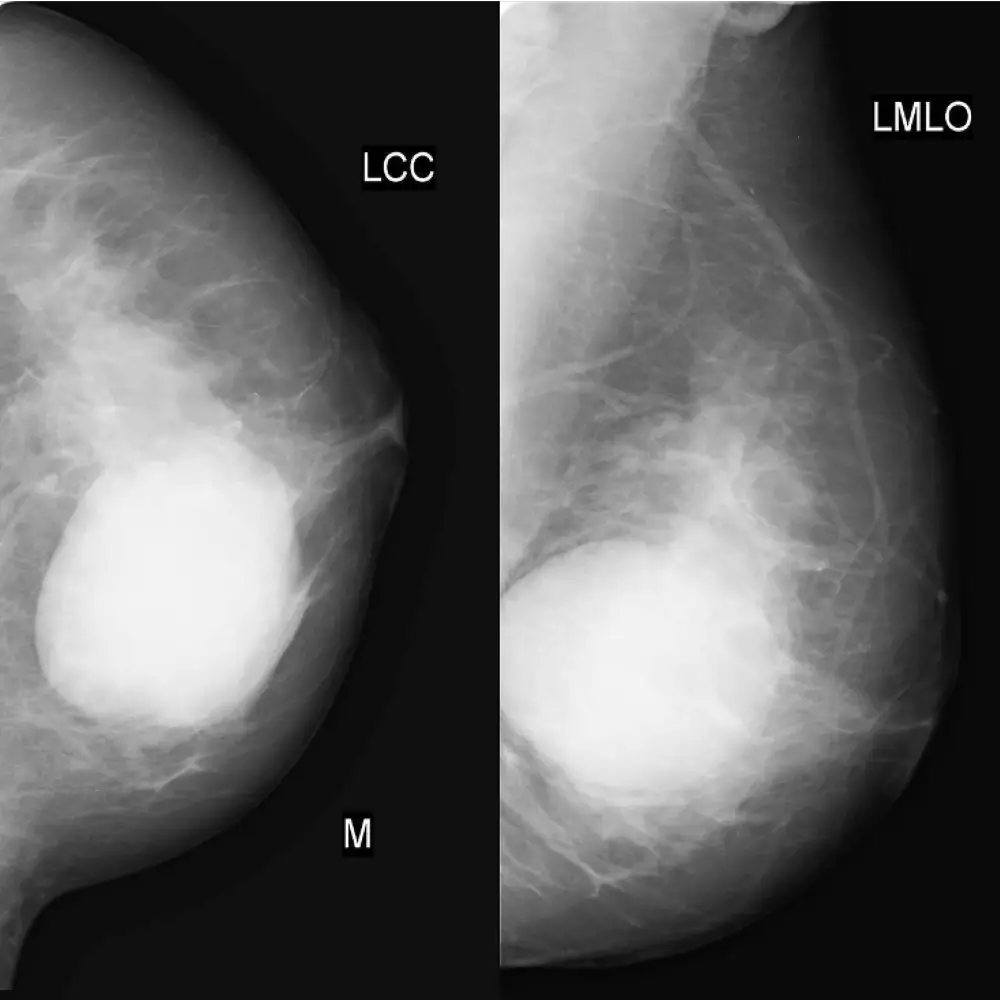

Screening